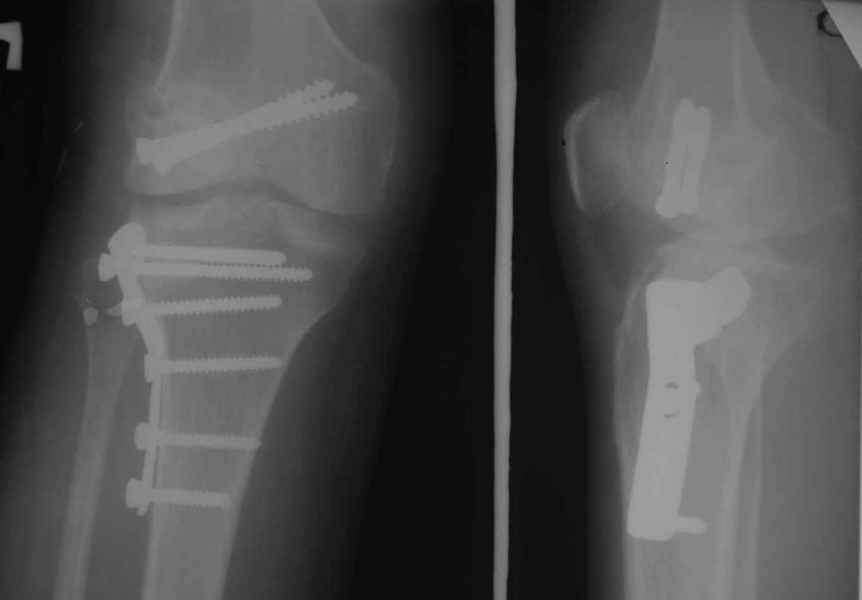

Как вариант решения прогрессирующей вальгусной деформации коленного сустава я бы предложил косую остеотомию дистального отдела бедра с фиксацией пластиной и компрессирующим винтом.

Взгляните на снимки , может быть это вам поможет.

Около 5 лет применяю этот тип дистальной остеотомии бедра для коррекции механической оси Н/К ( более 20 случаев) - достаточно эффективная операция.

Тут ситуация совсем другая. Деформация не около-, а самая что ни на есть внутрисуставная. Покорректировать внешний вид конечности путем остеотомии дистального отдела бедра и high tibia (плюс или минус клин, одномоментно-постепенно, аппарат-пластина-стержень - дело третье) не сильно сложно, но это не решение проблемы. У больной, по

сути отсуствует латеральный отдел коленного сустава, что требует костно-пластических вмешательств непосредственно на артикулирующих

поверхностях.